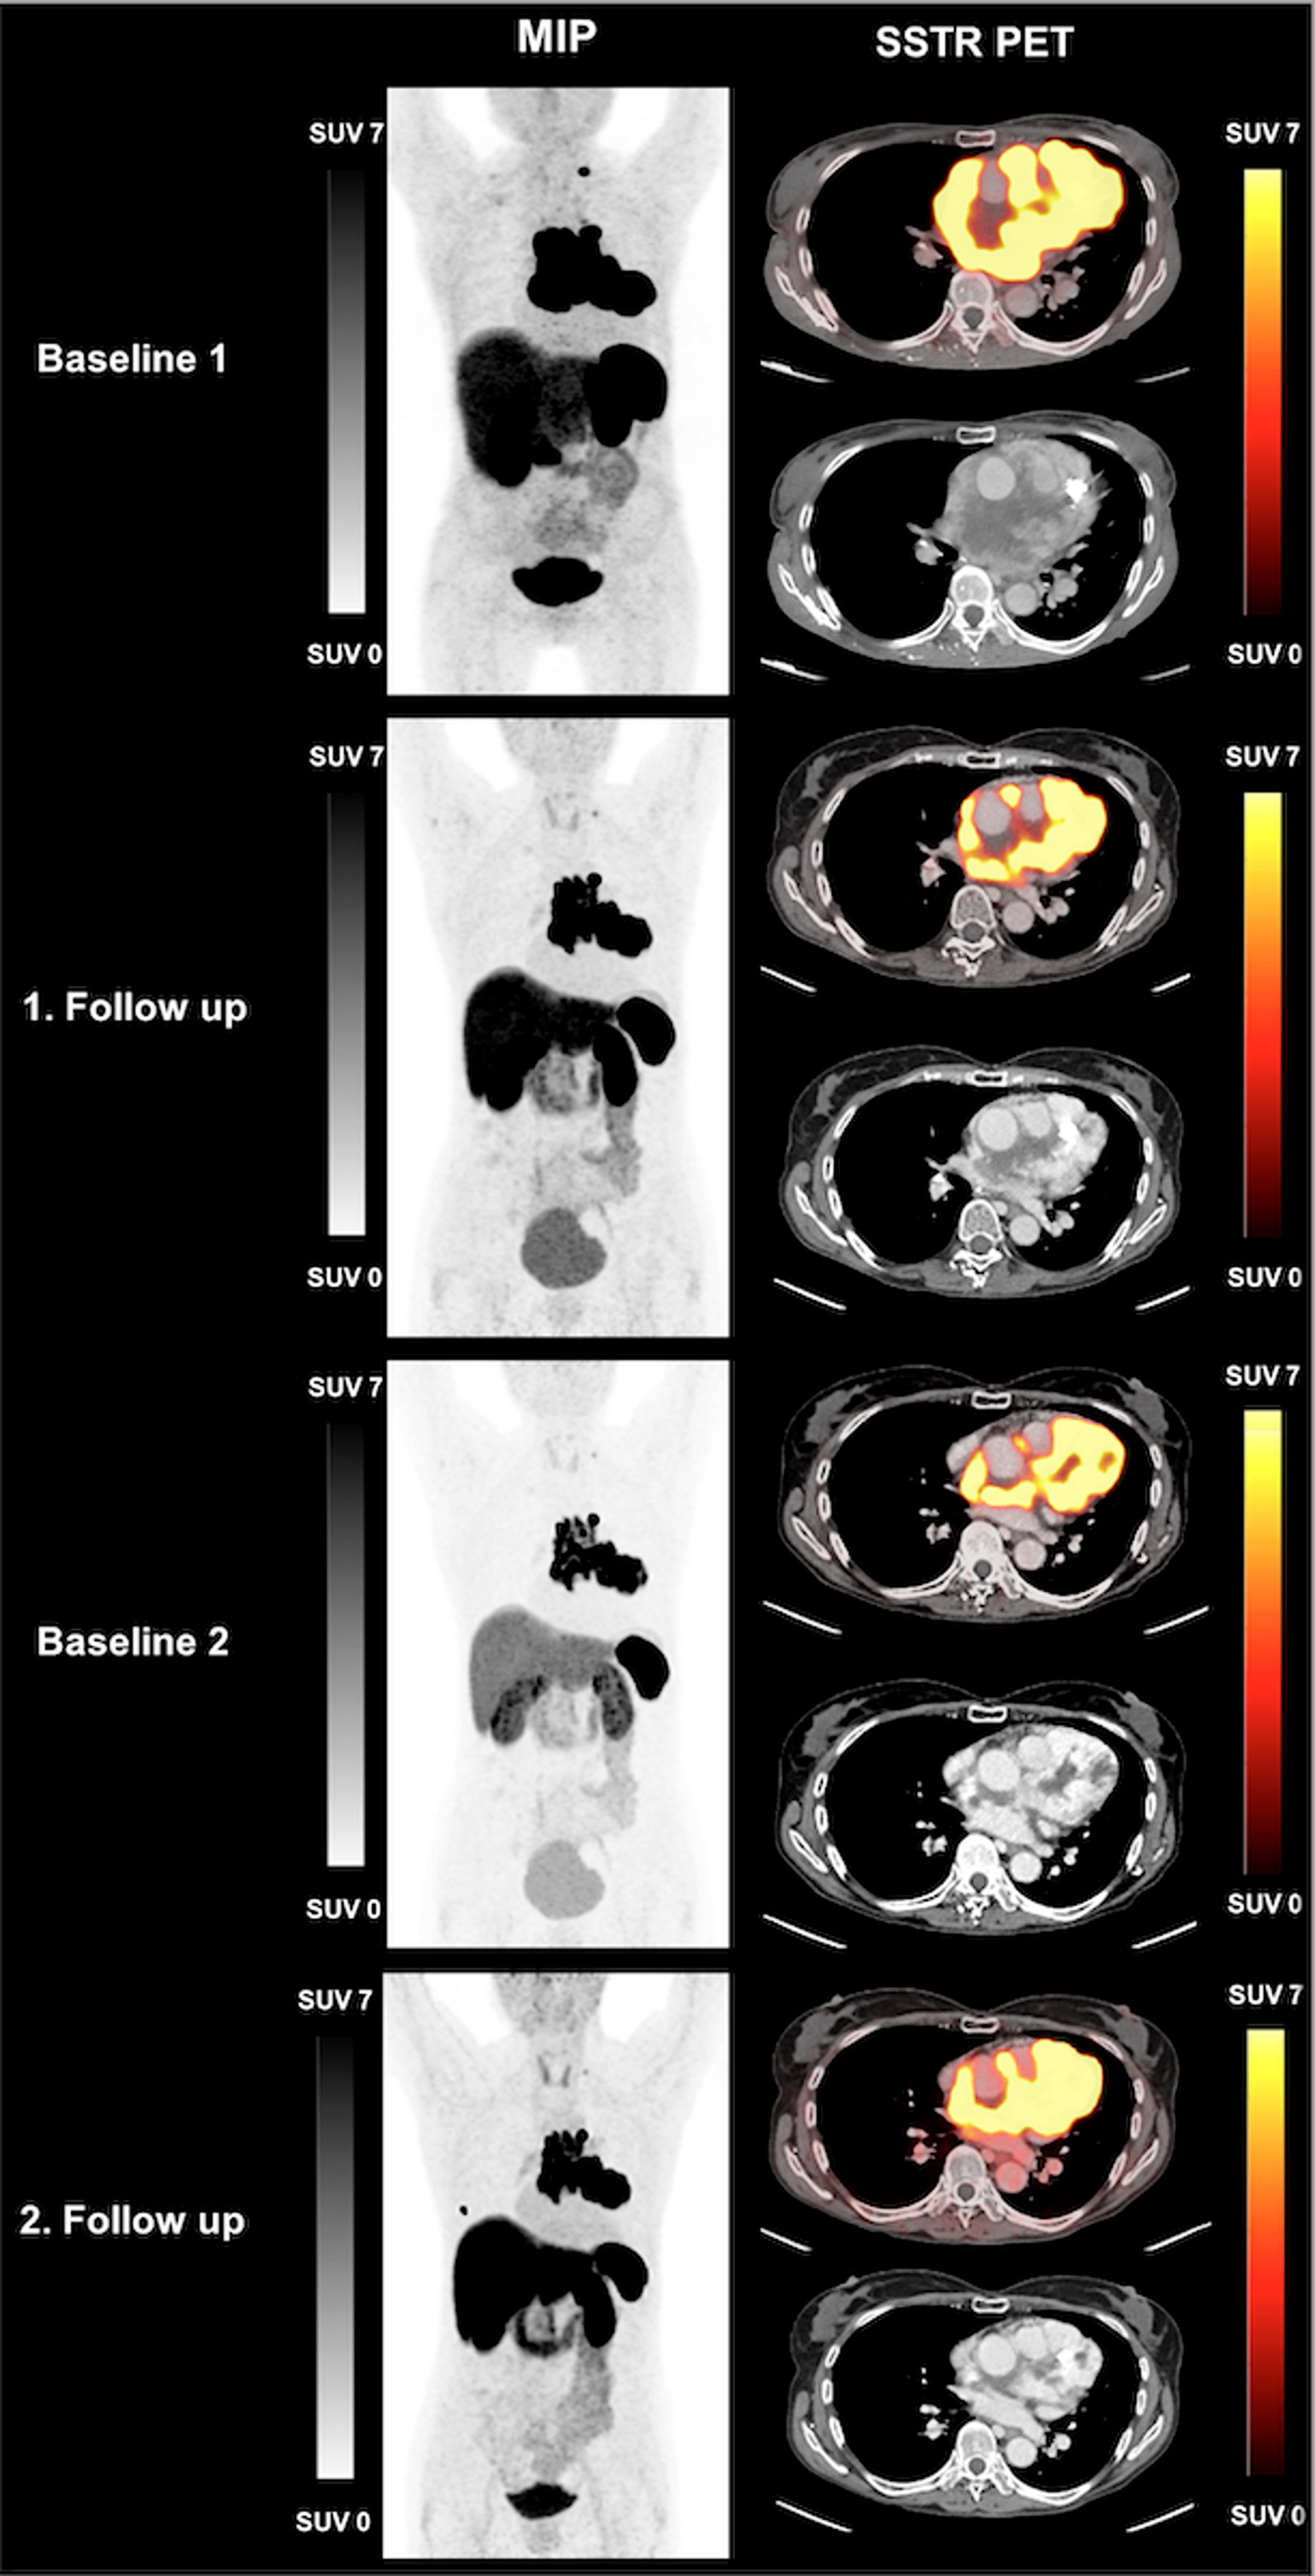

Fig. 2

MIP and axial SSTR PET of patient #5:The 68-year-old female patient was diagnosed with thoracic paraganglioma and underwent PRRT. After two cycles of PRRT TTV decreased from 564 mL (Baseline 1) to 485 mL (1. Follow up). After one year she received the fourth cycle of PRRT (rechallenge). TTV increased from 181 mL (Baseline 2) to 250 mL (2. Follow up), RECIST 1.1 defined the response as SD. The tracer uptake above the liver in the second follow up scan presented as a contamination of the skin